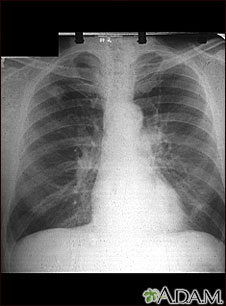

Esta radiografía muestra un adenocarcinoma del pulmón. Hay una zona clara redondeada en la parte superior del pulmón (lado izquierdo de la imagen), a nivel de la segunda costilla. La zona clara tiene bordes irregulares y poco definidos y su densidad no es uniforme. Las enfermedades que pueden presentar este tipo de resultado radiográfico son: tuberculosis o granuloma fungoso y tumores benignos o malignos.